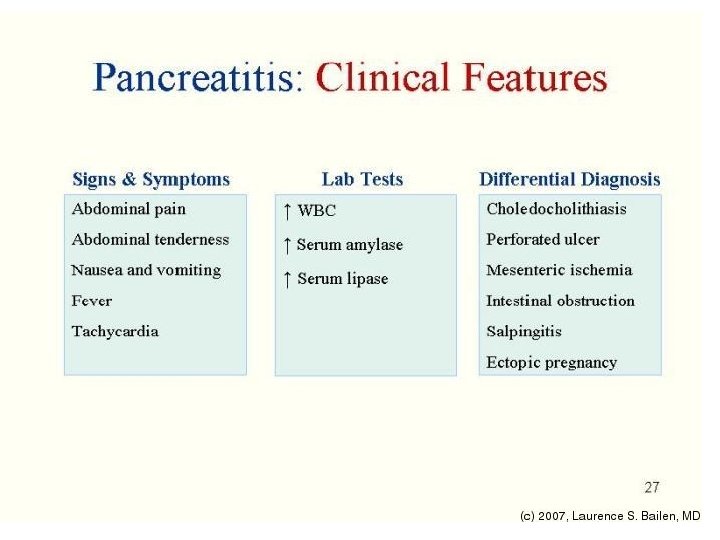

• DIAGNOZA DIFERENCIALE: - Appendisiti (ne fazen fillestare) - Pankreatiti - Patologjite renale dexter: infeksion apo kalkul ne ureter: *Anamneza *Ekzaminime laboratorik (urine) *Ekzaminime radiologjike te aparatit urinar

• DIAGNOZA DIFERENCIALE: - Me peritonitin akut nga ruptura te ndryshme si e apendiksit - Barra ekstrauterine - Pankreatit hemoragjik - Torsion ovarial

EKZAMINIMET LABORATORIKE: - Hemogram: Leukocitoze - Ekzaminimi i urines: per diagnoze diferenciale DIAGNOZA DIFERENCIALE: - Kolecistit - Kolika renale dexter - Ulcer gastroduodenale e perforuar - Okluzion intestinal